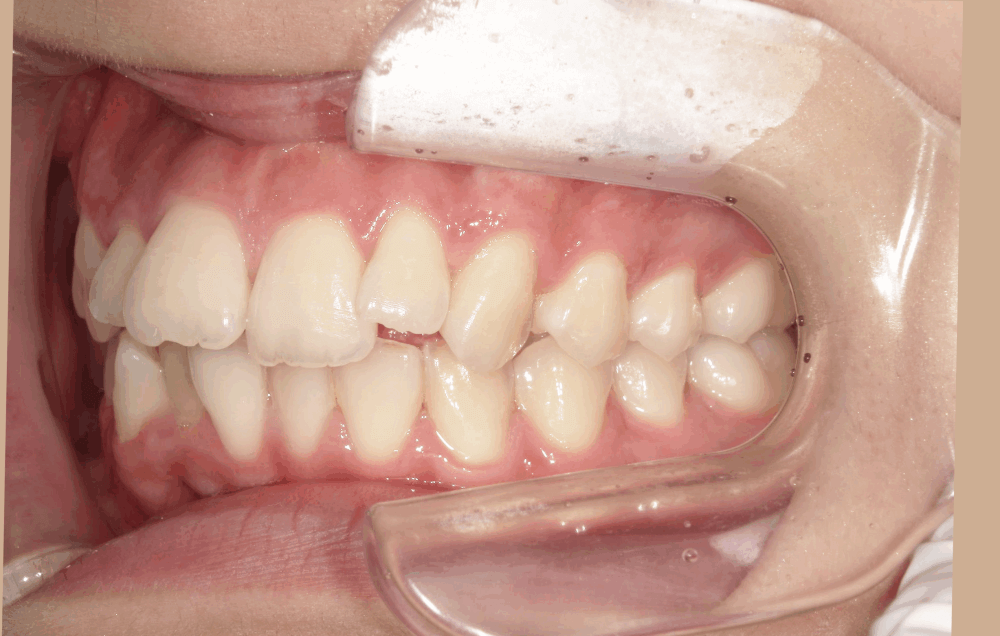

<初診時>

上の前歯の横の歯(前から2番目)が前方に飛び出しており、全体的にガタつき(叢生)が見られます。これは、歯の大きさに対してあごの幅がやや狭く、歯がきれいに並ぶスペースが足りないために起こります。

また、上下の前歯の中心(正中線)がわずかにずれており、奥歯のかみ合わせやあごの位置の影響がみられました。

上の前歯1本が前に出ており、いわゆる「出っ歯」の状態です。見た目の印象だけでなく、口を閉じにくい・前歯で噛みにくいなどの機能面への影響もありました。

横から見ると、Eライン(鼻先とあご先を結ぶ線)より内側に口元があります。しかし、口を閉じるときに力が入ることでリップラインが不自然になり、少しふくらんで見える状態でした。患者様自身もこの「口元の力み」を気にされており、原因は上顎前歯の突出(出っ歯)によるものでした。